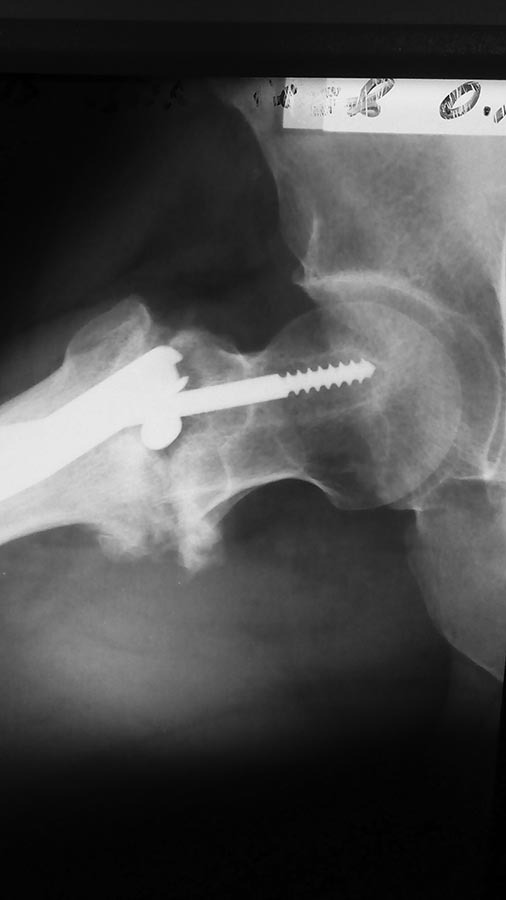

[Ortho] Чрезвертельный неправильно консолидирующийся перелом

Травма, МОС PFN в апреле 2015. В июне миграция шеечного винта, удаление

его. На данный момент в течение недели усилились боли, ходит с костылём

с частичной нагрузкой на конечность. Имеем вот такой снимок.